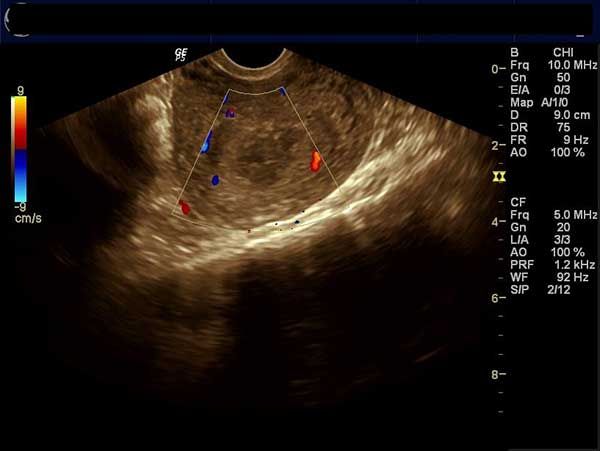

This young lady has abdominal pain and chest discomfort.She was undergoing treatment for infertility.What is your diagnosis?